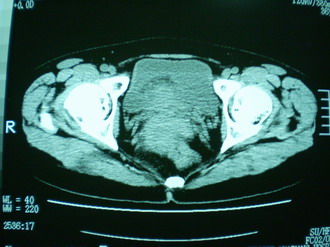

子宫增大,内可见类三角形低密度区,子宫后方可见类圆形团块状影,内部密度不均匀,可见靶样结构,结合病史考虑1子宫后方宫外孕(宫内假孕囊形成)2子宫肌瘤合并妊娠

子宫明显前倾,增大,宫颈增大呈分叶状。子宫直肠窝见不规则形水样低密度。(膀胱胀尿不理想)

考虑:1、宫颈部占位;

2、子宫直肠窝少量积液(盆腔炎所致)。

考虑:1、宫颈部占位(宫颈癌?);

2、子宫直肠窝少量积液。